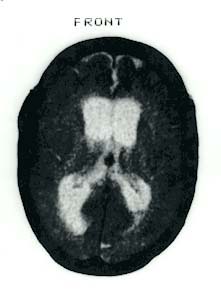

Photo: Computertomographie des menschlichen Gehirns